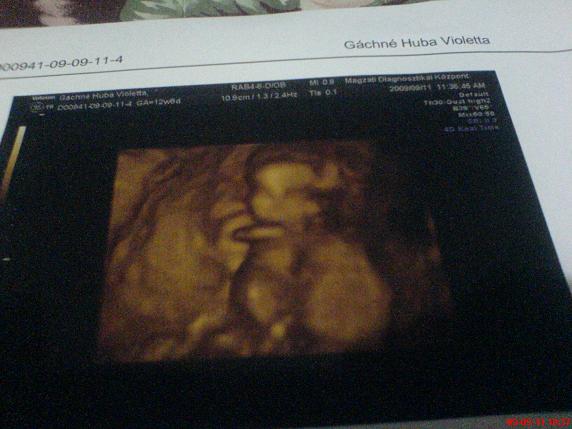

Jaaa, és erősen "kuki-gyanús" a bébi!!! :D:D:D

Gyönyörűűűű! képek! Gratula a kis kukacoshoz,egyben üdv a fiús (is) anyák táborában! :lol:

Ja és kaptam dvd-t, de hát hogy őszinte legyek, nem gondoltam, hogy a 20 percből fél percre kapcsol át 4 d-be... :shock: :shock: :shock: :shock: :shock: azért a 14 ezerért azt hittem, legalább 10 perc lesz a 4 d....

Tiszta apja!!!:D:D:D Kép

Vivi, a te babád is nagyon édes!!! És még egy fiúcska! :) :)

A fiammal a terhesség 33.hetéig a Kondér doktor volt az orvosom, anno a fiamnál is Ő állapította meg, hogy kukacos! És nem tévedett! :)))

Vivi: nagyon szépek az eredményeid, az enyémek is majdnem megegyeznek. Engem is a Kondér dr. UH-zott múlt pénteken, nagyon hozzáértőnek tűnt.

Én valószínűleg a Magzati Diagnosztikai Kp-ban fogom csináltatni a 18. heti genetikai UH-t, mert tényleg ott a legmegbízhatóbbak, bár én a saját orvosomban is megbízom, a kórházban viszont tuti nincs 4D.